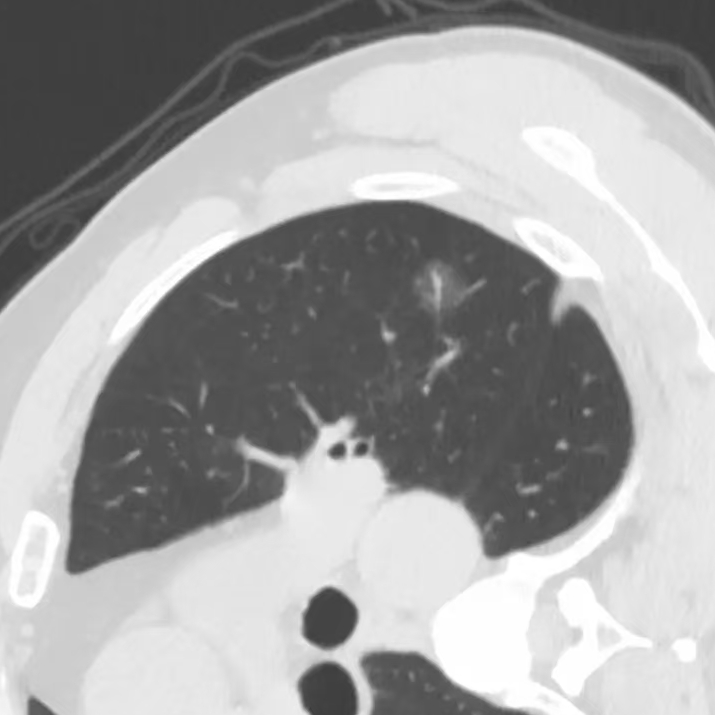

健康直通车: 健康是生命的宝贵财富,也是幸福生活的基石。为了更好地服务广大百姓,传播健康知识,葫芦岛市第二人民医院推出“健康直通车”专题栏目,将专业的医学知识以通俗易懂的方式传递给每一位市民,掌握科学的疾病预防方法,共同构筑健康中国的坚实基石。 什么是肺结节 肺结节是指肺内直径小于或等于3cm的类圆形或不规则形病灶,影像学表现为密度增高的阴影。大于3cm的称肿块。肺结节依其密度不同可分为实性结节、部分实性结节、磨玻璃结节,其中部分实性结节的恶性可能性最大,磨玻璃结节次之,实性结节尤其是小的实性结节结节最可能是良性的。 肺结节的常见病因 1、良性(约90%) 🔸 感染:结核、真菌、细菌性肺炎后遗留的瘢痕; 🔸 非感染:错构瘤(良性肿瘤)、炎性假瘤、血管瘤等。 2、恶性(约10%) 🔸原发性肺癌(如腺癌、鳞癌); 🔸转移性肿瘤(其他器官癌症转移至肺)。 如何根据影像判断肺结节性质 1、依据结节大小判断 🔸小于0.5cm的肺结节绝大多数都是良性的,属于微小结节。即使部分小于0.5cm肺结节是恶性的,但是适当的观察不影响预后。每年复查一次胸部CT就可以。 🔸大于0.5cm持续存在的纯磨玻璃结节,观察6个月,若持续存在,不管有无进展均多数是恶性的,视患者意愿,手术可以立即做也可观察至进展再做,不影响预后。 🔸大于0.8cm的部分实性结节恶性可能性非常大,应积极评估结节边缘毛刺、分叶、胸膜凹陷等征象。 🔸若实性部分大于0.5cm,恶性率显著提高。若在3~6个月随访期间实性部分增大或者总体部分增大,都可以考虑手术切除。而即使小于0.8cm的部分实性结节也需3个月就复查对比。 2、依据肺结节形态 如CT上提示病灶形态不规则、毛刺、分叶、胸膜凹陷、空泡征、血管集束征等,符合恶性肿瘤的征象。 🔸结节与正常肺组织之间界限非常清楚的恶性可能性大。 🔸结节密度不均呈混杂密度或均匀较大纯磨玻璃结节也基本是恶性的。 🔸有胸膜牵拉(不管是肺表面的脏层胸膜还是叶间裂部位的胸膜)的恶性可能性大。 🔸结节有浅分叶、细毛刺,密度较高而与周围肺组织边界不清的恶性可能性大。 🔸磨玻璃或混合磨玻璃结节存在小空洞的恶性可能性大。 🔸影像上似慢性炎表现,而没有炎症相关的其他异常,特别当所谓炎症区域内部或一侧与正常肺组织之间界限非常清楚的基本上是恶性的。 3、从结节发展情况来看 所有随访中增大进展的都需要考虑恶性可能,不进展而持续存在的纯磨玻璃结节也需考虑恶性。 葫芦岛市第二人民医院肺结节诊治中心孙振教授深耕肺结节领域四十余载,凭借对临床实践的执着钻研与深厚积淀,在肺结节精准诊断及鉴别诊断领域形成独到见解。他系统总结海量临床病例,创新性提炼出一套科学化、规范化的肺结节全周期诊疗体系,尤其在早期微小结节的影像特征识别、良恶性风险分层等方面积累了丰富经验,为众多患者提供了精准、高效的诊疗方案。 人民医院·人民名医 孙振 主任医师 三级教授 ·葫芦岛市第二人民医院胸外科主任、肺结节诊治中心主任 ·中国医科大学客座教授 ·原央企总医院著名胸外科专家 ·辽宁省医学会胸外科委员 ·辽宁省抗癌协会肺癌专业委员会委员 ·辽宁省细胞生物学学会食管癌专业委员会理事 ·主持多项科研成果获科技成果奖、科技进步奖、国家专科奖项 医学成就 从事胸外科临床工作近40年,担任胸外科首席专家及科室主任20余年,是我省胸外科领军人物,推动肺癌、食管癌等胸部肿瘤外科的规范化诊疗,在央企总医院牵头成立了肺结节诊疗中心,率先开展CT引导下肺内小结节定位切除,既确切完整切除肺内小结节,又降低肺功能损害。 专业特色 擅长肺癌、食管癌的外科手术和综合治疗,在各类高难度胸外伤手术治疗、胸腔镜微创手术、胸腺瘤手术及复杂并发症处理方面具有高深造诣,尤其擅长肺癌早期诊断,胸部小结节CT早期肺癌的鉴别等。完成各类高难度胸外科手术5000余例,其中微创手术占比达90%,治愈率达98%,多项业务填补省内空白。 开展的高难手术 胸腔镜肺部结节微创手术、肺癌根治术、食管癌根治术、各种纵隔肿瘤切除术、胸骨后甲状腺手术及胸部复合性外伤的抢救手术等。